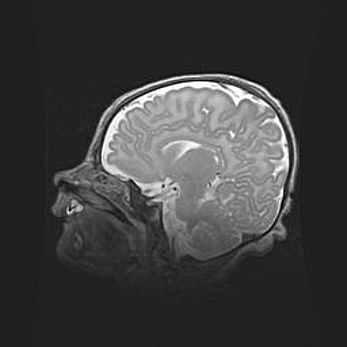

Аномалия Денди-Уокера. Признаки гипоплазии мозолистого тела.

Возраст: 5 месяцев 3 дня

Вес: 5550 г

Пол: мужской

Окружность головы: 39 см

Срок гестации: 40 недель

Аномалия Денди-Уокера – это порок развития головного мозга, для которого характерна триада симптомов: гипотрофия или аплазия червя мозжечка и/или полушарий мозжечка, расширение четвёртого желудочка с формированием ликворной кисты задней черепной ямки, гипертензионная гидроцефалия различной степени.

Гипоплазия мозолистого тела относится к дефектам внутриутробного этапа развития мозговой ткани, возникающим в процессе закладки структур головного мозга, что происходит на начальных этапах развития эмбриона.